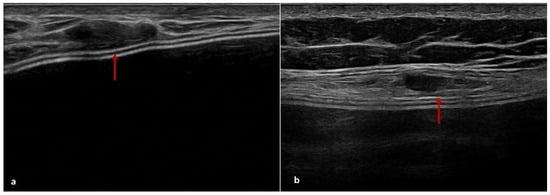

4.2. US Features of ADM

| US | Derived from pig dermis | Ten patients (16%) | Seven patients (11%) | Seven patients (11%) | Five cases of peri-capsular thickening and two cases with pseudonodular areas at T2 |